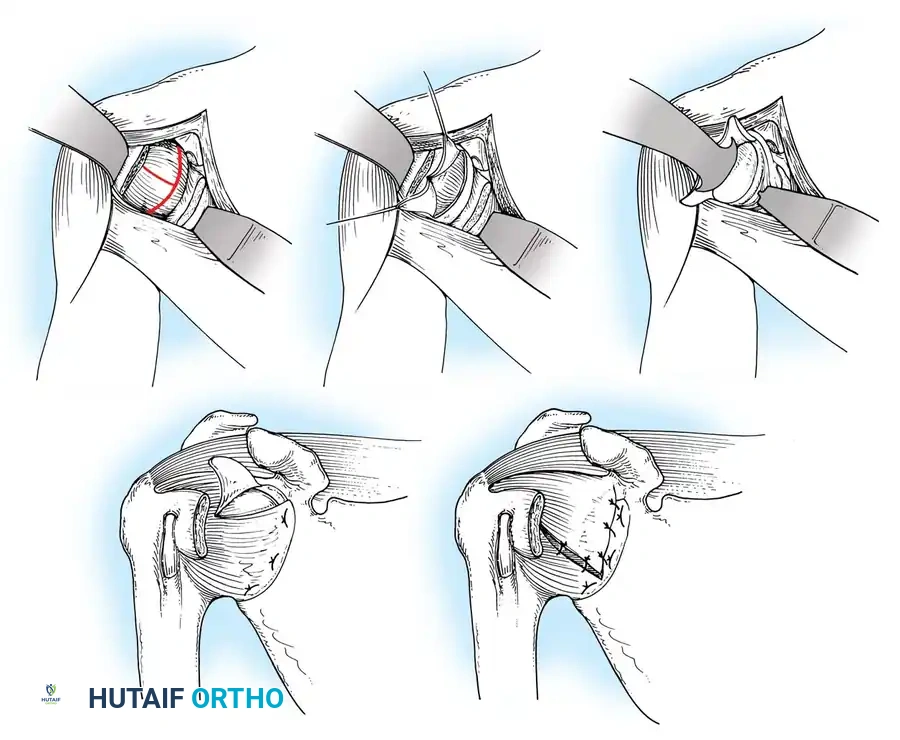

Capsulotomy and Joint Inspection

A vertical or T-shaped capsulotomy is performed based on the degree of capsular laxity and the planned shift.

- For a standard Bankart repair with an inferior capsular shift, a vertical incision is made 1 cm medial to the humeral articular margin. A horizontal limb can be added to create superior and inferior capsular flaps.

- Tagging sutures are placed in the capsular flaps for traction.

- A Fukuda retractor is placed within the joint to retract the humeral head laterally and posteriorly, exposing the anterior glenoid rim and labrum.

Glenoid Preparation and Labral Repair

The essential step in restoring stability is the anatomical reduction of the capsulolabral complex to a bleeding bone bed on the anterior glenoid rim.

- Debridement: The anterior glenoid neck is decorticated using a motorized burr, rasp, or osteotome to create a bleeding cancellous bed. This promotes robust biological healing of the repaired labrum.

- Mobilization: The scarred, medially displaced labrum (ALPSA lesion) must be fully mobilized using a periosteal elevator until the subscapularis muscle belly is visible anteriorly. The tissue must float freely to be shifted superiorly and laterally.

- Anchor Placement: Suture anchors (typically 3 to 4) are placed along the articular margin of the anteroinferior glenoid (from the 5:30 to 3:00 positions for a right shoulder). Anchors must be inserted at a 45-degree angle to the articular surface to maximize pullout strength and avoid joint penetration.

Capsular Shift and Closure

To address capsular redundancy, an inferior capsular shift is performed.

- The arm is positioned in 30 to 45 degrees of abduction and 20 degrees of external rotation.

- The inferior capsular flap is advanced superiorly and laterally, tensioning the IGHL complex. The sutures from the anchors are passed through the shifted capsule and tied.

- The superior flap is then brought down over the inferior flap in a "pants-over-vest" fashion to reinforce the anterior wall and close the rotator interval.

- The subscapularis split is loosely approximated with absorbable sutures. The deltopectoral interval is closed over a suction drain (if necessary), followed by routine subcutaneous and skin closure.